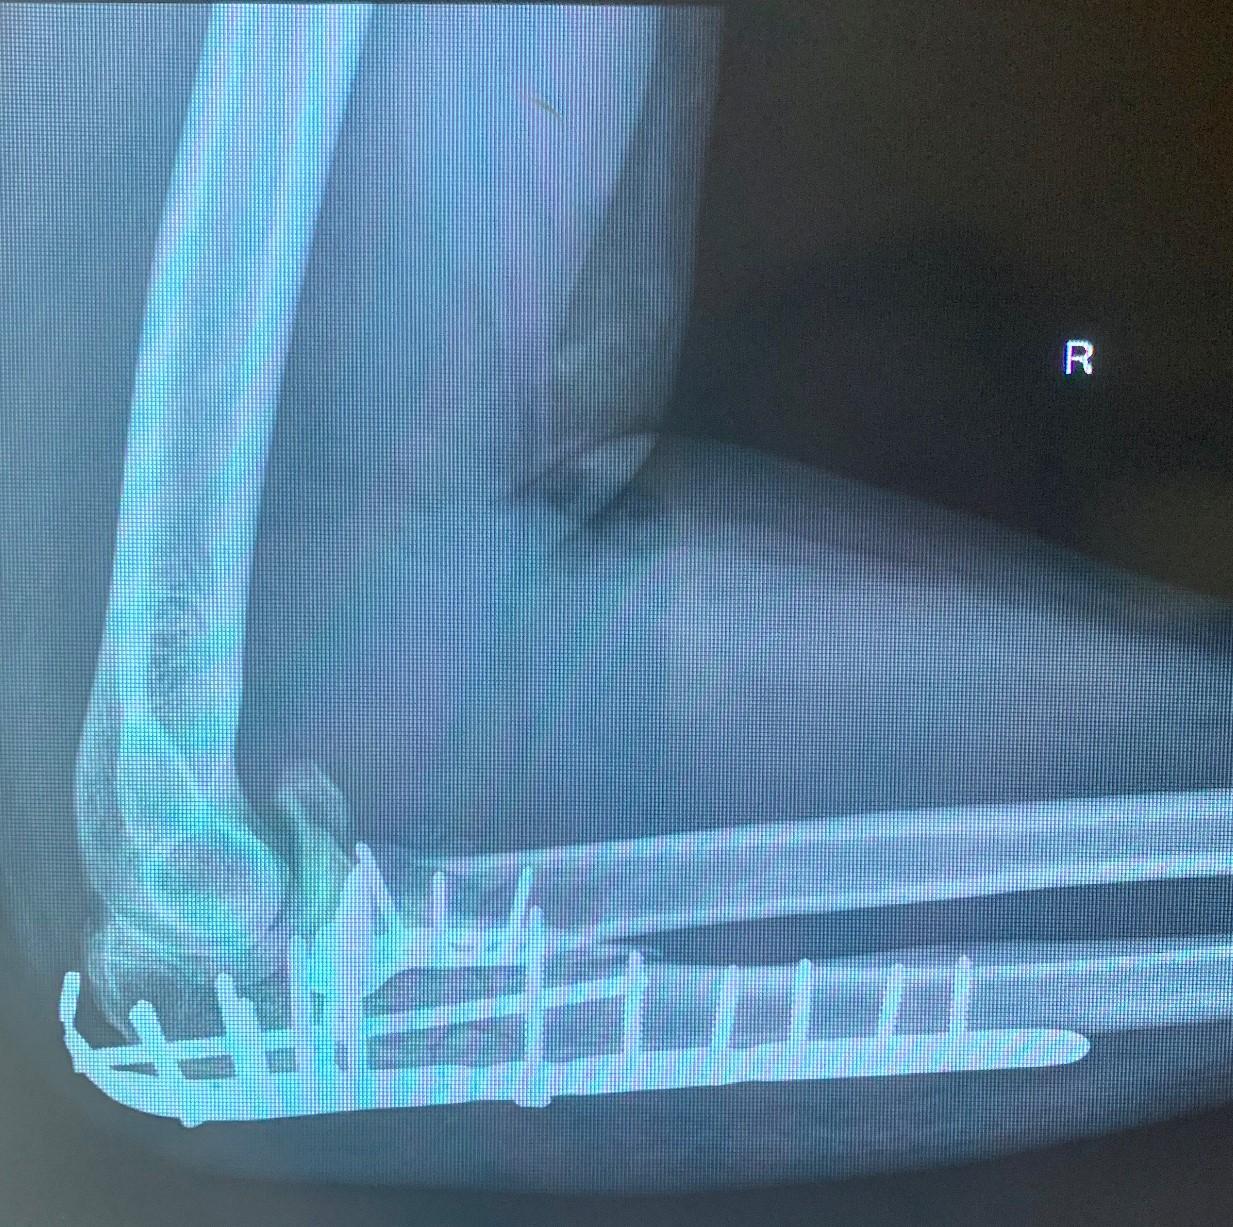

This 44yo gentleman, who lives about 5 hours drive away from Perth, fell 3.5m from a ladder 3 months ago. He landed directly on his elbow, resulting in a dislocation of the elbow joint and significant fractures to the proximal ulna and radius. He underwent reconstructive surgery (ORIF) to both bones, and his X-ray image below shows the extensive metalwork still in place.